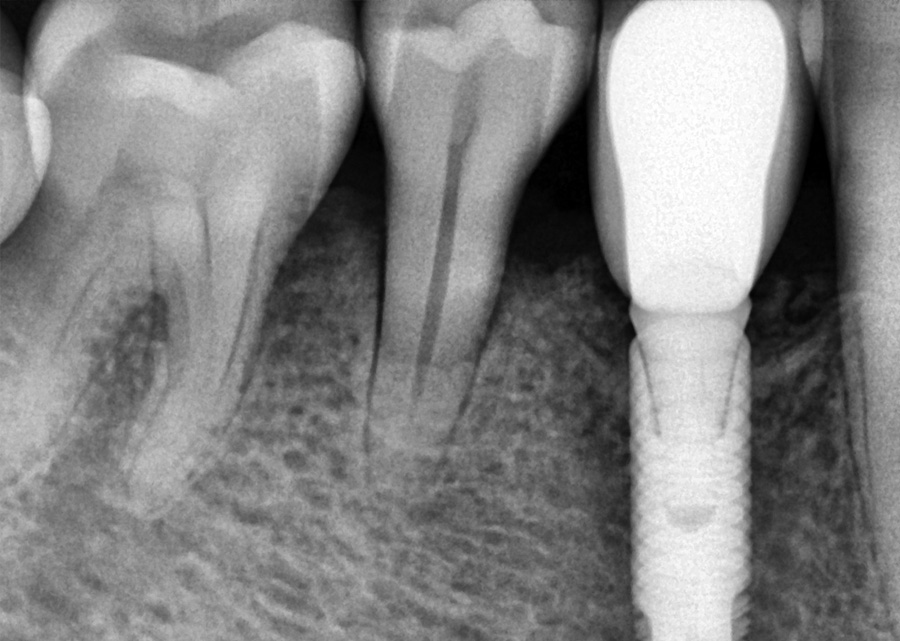

Orthodontic Treatment X-ray - Before

After Series of Teeth Extractions, Upper Left Canine Unerupted.

Ready to Start Ortho Treatment